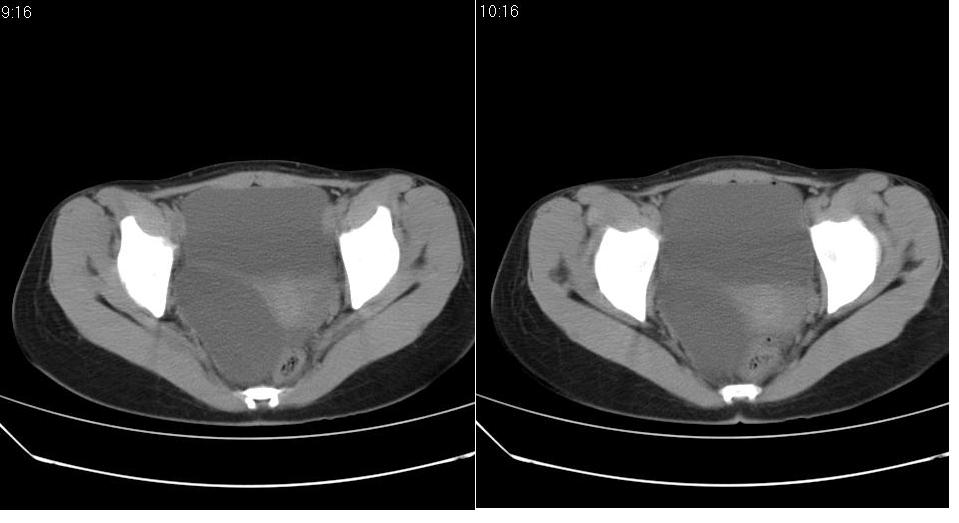

标题: CT22811:女 36岁,B超提示右侧附件囊性占位。 [打印本页]

标题: CT22811:女 36岁,B超提示右侧附件囊性占位。

右侧卵巢囊肿

右侧卵巢囊肿。

手术结果证实为右侧输卵管囊肿。

输卵管囊肿罕见,从影像上无法同卵巢囊肿区分。

输卵管囊肿一般是指输卵管受病原体感染以后,由于白细胞的浸润形成内膜肿胀、间质水肿、渗出,输卵管粘膜上皮脱落,如果输卵管急性期炎症没得到及时有效的治疗就形成了输卵管积脓。输卵管积脓在炎症消退后,脓液逐渐被吸收,腔内积液由脓性变为浆液性,则成为输卵管囊肿。

还是报右侧附件区良性囊性占位性改变       至于输尿管或卵巢囊肿不太好鉴别